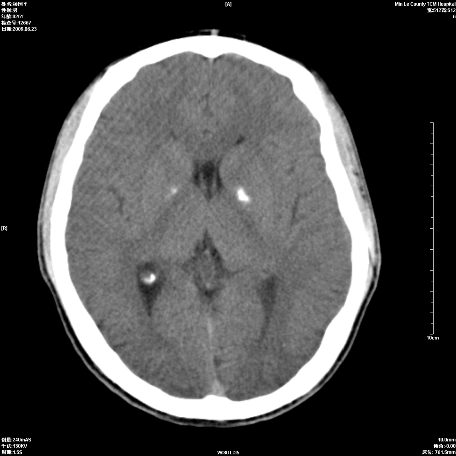

以下是引用随光逐影在2009-6-23 14:30:00的发言:[br]1)颅脑ct轴位平扫颅内未见明确异常。2)左侧额部头皮软组织肿胀。[br][br](双侧苍白球见对称性钙斑,透明隔间腔与vergae腔并存)